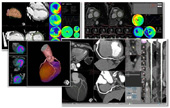

■心臓解析オプション

新しくなった「CT心機能解析」「MR心機能解析」では従来の操作ステップを5分の1に短縮。心筋の内壁,外壁のオートトレース機能が向上し,修正作業を大幅に削減しました。ワイドモニタ対応レイアウトで,読影効率も大幅にアップします。「MR心機能解析」ではEF等の心機能解析に加え,Black Blood,Delayed Enhancement等を同時表示し,効率的な解析が可能です。

さらに,わずか数ステップでCTの形態情報とSPECTの機能情報を3次元的に融合する「CT-SPECT 3D Fusion」(WIP)もラインナップに加わりました。

高精度なフルオート処理で定評のある「CT冠動脈解析」とともに,CT,MRIだけでなく,SPECTまで対応した「ZIOSTATION」で心臓検査を包括的にサポートします。

心臓解析オプション

【画像クリックで拡大表示します 】